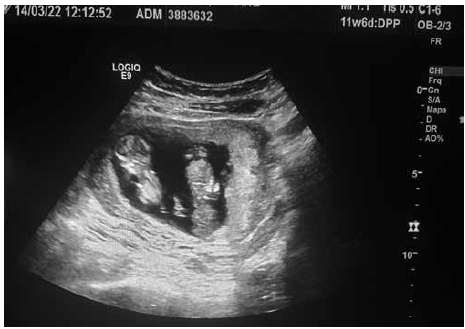

Paciente com IG de 12 semanas pela DUM veio à medicina fetal para realização de seu primeiro ultrassom obstétrico. Identificadas as figuras 1 e 2 (em ângulos e posições diferentes), conforme ilustrado.

Figura 1

Figura 2

Com base nas imagens em conjunto, assinale o diagnóstico correto é: